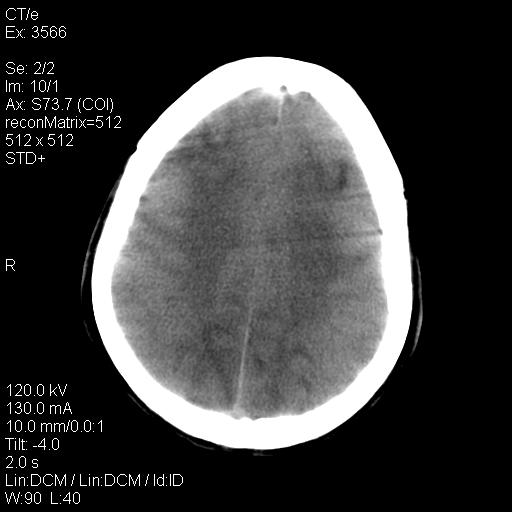

标题: CT9947:女,20岁,妊娠9个月,突然癫痫症状 [打印本页]

标题: CT9947:女,20岁,妊娠9个月,突然癫痫症状

双侧脑白质缺血缺氧性改变,并高度可疑“蛛网膜下腔出血”。

后可复性脑病,

考虑 妊娠子痫或妊高征

双侧脑白质缺血缺氧性改变.

考虑先兆子痫\\子痫致he,建议mri除外有无合并静脉窦血栓形成.

考虑pres

的确应该考虑可逆性后部脑病综合症--pres。感谢天南地北老师的指引,又学了一招儿,开心,呵呵!

考虑可逆性后部脑病综合症

支持pres